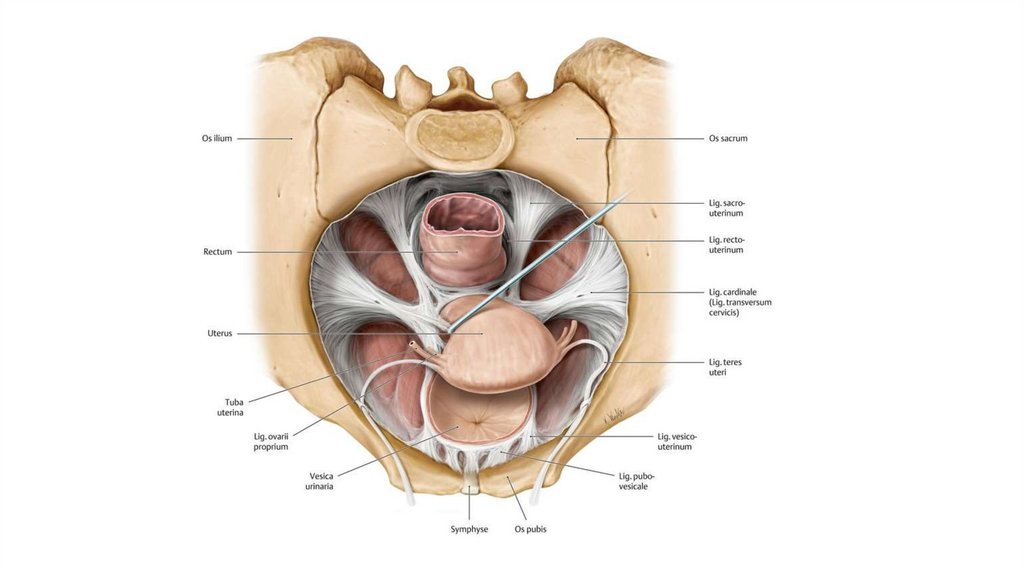

Анатомия малого таза: детальные схемы и изображения